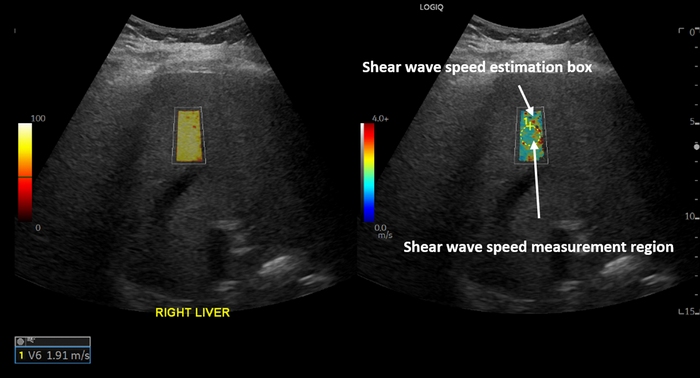

image: A 55-year-old female with a history of COVID-19 infection 38 weeks before the date of ultrasound shear wave elastography. The shear wave speed of 1.91 m/s corresponds to Young’s modulus of 10.94 kPa which indicates abnormally high liver stiffness and may reflect chronic liver injury. view more

Credit: RSNA and Firouzeh Heidari, M.D.

In the retrospective study, the researchers compared liver stiffness of patients with a history of COVID-19 infection to two control groups. All patients underwent ultrasound shear wave elastography between 2019 and 2022 at Massachusetts General Hospital. Shear wave elastography is a specialized technique that uses sound waves to measure the stiffness of tissue.